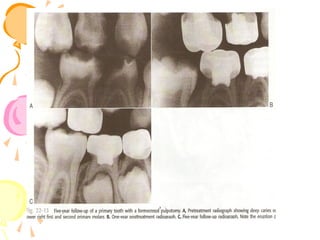

Non-vital pulp therapy⎯primary tooth. (a) A carious, but restorable, non-vital primary molar.

(b) Caries is eliminated and access made to the pulp. Gentle canal debridement is undertaken

with smal files and irrigation. (c) Disinfection of the canal system. A pledget of cotton wool

barely moistened with ledermix is sealed into the pulp chamber for 7-10 days. (d) The tooth

is reopened at a second visit, and after irrigation and drying, a soft mixture of slow-setting

zinc oxideeugenol cement is gently packed into the canals with the cotton-wool

pledget. (e) The pulp chamber is packed with accelerated zinc oxideeugenol cement before

.definitive restoration of the tooth

a) Periapical radiograph)

showing files placed in the root

canals of left lower second primary

molar

b) Root canals have been filled )

with pure zinc oxide eugenol

•Root canal filling in an upper

primary central incisor